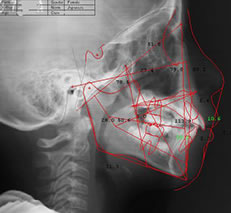

セファロ

セファロは、顎の骨や頭部全体のバランスを正確に分析するためのレントゲン装置です。特に成長期にある子どもの矯正治療では、顔全体の骨格を考慮することが非常に重要です。セファロでの計測は、医学的根拠に基づいた診断と治療の基盤となります。